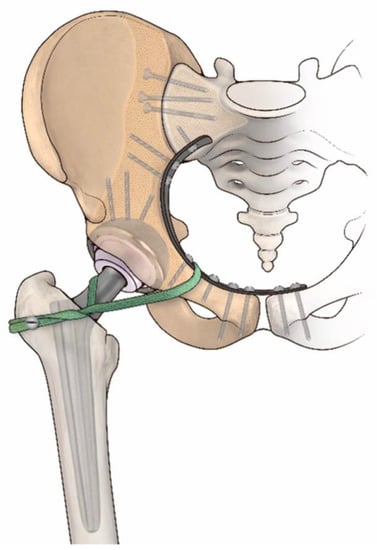

- Fujishiro, T.; Nishikawa, T.; Takikawa, S.; Saegusa, Y.; Yoshiya, S.; Kurosaka, M. Reconstruction of the Iliofemoral Ligament with an Artificial Ligament for Recurrent Anterior Dislocation of Total Hip Arthroplasty. J. Arthroplast. 2003, 18, 524–527. [Google Scholar] [CrossRef]

- Aota, S.; Kikuchi, S.; Ohashi, H.; Kitano, N.; Hakozaki, M.; Konno, S. Soft Tissue Reinforcement with a Leeds-Keio Artificial Ligament in Revision Surgery for Dislocated Total Hip Arthroplasty. HIP Int. 2018, 28, 324–329. [Google Scholar] [CrossRef] [PubMed]